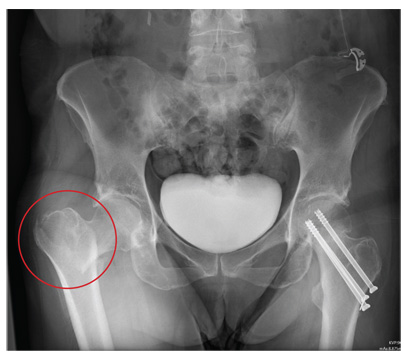

A 55-year-old woman is transferred to your facility with injuries sustained in a motor vehicle collision. She was an unrestrained front-seat passenger in a vehicle that rear-ended another vehicle. There was no airbag deployment, and the patient believes she struck her face on the windshield. At the outside facility, it was determined that she had a cervical fracture and facial fractures. Upon arrival at your facility, she is complaining of bilateral hip pain as well. Her medical history is significant for coronary artery disease, several myocardial infarctions, hypertension, and stroke. She has a pacemaker. Six months ago, she had an open reduction internal fixation of her left hip for a fracture she sustained in a fall. Primary survey reveals a female who is uncomfortable but alert and oriented. Vital signs are normal. She has some facial swelling and bruising. Her heart and lungs are clear; abdomen is benign. She is able to move her upper extremities with-out any problems. She has limited movement of her lower extremities due to pain in her pelvis. She is able to move both feet and toes, and distal pulses and sensation are intact. No obvious leg shortening is noted. A portable radiograph of the pelvis is obtained. What is your impression?

The radiograph demonstrates evidence of contrast material within the bladder. There is evidence of fixation of an old subcapital femoral neck fracture on the left.

There is an acute, mildly displaced right intertrochanteric fracture of the right hip. The orthopedic service was consulted, and plans were established to subsequently fix this fracture surgically.